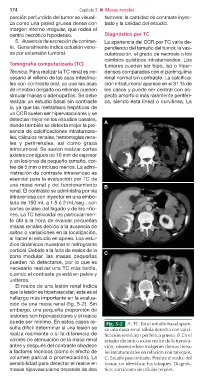

sencia de calcificaciones intratumora- Fig. 5-2 A: TC. En el estudio basal apare-

les, cálculos renales, hemorragias rena- ce una masa renal sólida derecha con calci-

les y perirrenales, así como grasa ficación semilunar periférica gruesa. B: En el

intratumoral. Se suelen realizar cortes estudio dinámico existe realce de la tumora-

axiales contiguos de 10 mm de espesor ción, observándose imágenes densas linea-

y, en lesiones de pequeño tamaño, cor- les intratumorales en relación con tabiques.

tes de 5 mm o incluso menos. La admi- C: Estudio poscontraste. Persiste el realce del

nistración de contraste intravenoso es tumor, sin identificar los tabiques. Diagnós-

esencial para la evaluación por TC de tico: carcinoma de células renales.

El realce de una lesión renal indica

que la lesión es hipervascular; éste es el

hallazgo más importante en la evalua-

ción de una masa renal (fig. 5-2). Sin